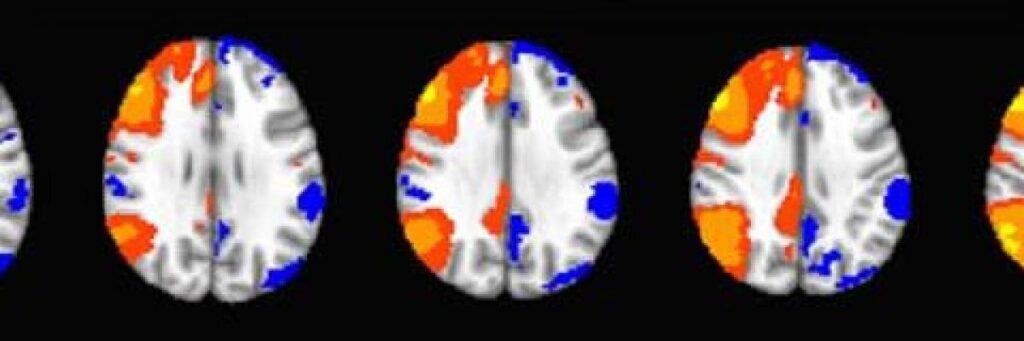

La principal ventaja de un sistema 7T, como el Varian Magnex, es su capacidad para ofrecer imágenes de tejidos con un nivel de resolución excepcional. La declaración de que el magnetismo permite 'MRI y MRS de tejidos a un alto nivel de resolución' subraya esta fortaleza. En el contexto de la investigación con animales pequeños, donde las estructuras de interés pueden ser muy pequeñas (por ejemplo, regiones cerebrales específicas en un ratón), la alta resolución es indispensable. Permite la delineación precisa de anatomía fina, la identificación de lesiones pequeñas o cambios patológicos, y el seguimiento detallado del desarrollo de enfermedades.

La combinación de MRI y MRS es particularmente poderosa para la investigación de enfermedades. La MRI puede mostrar los cambios estructurales o volumétricos asociados con una patología, mientras que la MRS puede revelar alteraciones en el metabolismo celular, la energía o la neurotransmisión que preceden o acompañan a los cambios anatómicos visibles. Por ejemplo, en modelos de enfermedades neurodegenerativas, la MRS puede detectar disminuciones en ciertos metabolitos neuronales o aumentos en marcadores de inflamación, mientras que la MRI puede mostrar atrofia cerebral o lesiones. La capacidad de monitorear tanto 'cambios anatómicos como metabólicos' de forma conjunta proporciona una comprensión mucho más completa del proceso de la enfermedad.

El sistema Varian 7T está disponible para la comunidad de investigación y está diseñado para permitir el 'monitoreo de vanguardia del desarrollo y tratamiento de enfermedades' en modelos animales pequeños. Esto abarca un amplio espectro de áreas de investigación biomédica. Dado que la MRI y la MRS son herramientas poderosas para estudiar el cerebro, este sistema es invaluable para la investigación en neurociencia, incluyendo: